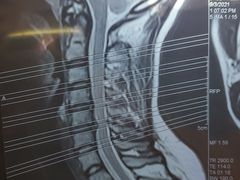

• 航天中心医院

• -航天中心医院

木林森 | 21-10-12

november晴朗的天 | 21-09-24

Angelina安吉 | 21-09-06

猪猪 | 21-09-02

Catherine麥子 | 21-09-02

代代_9662 | 21-08-30

azx | 21-08-04

兔子1.26 | 21-08-01